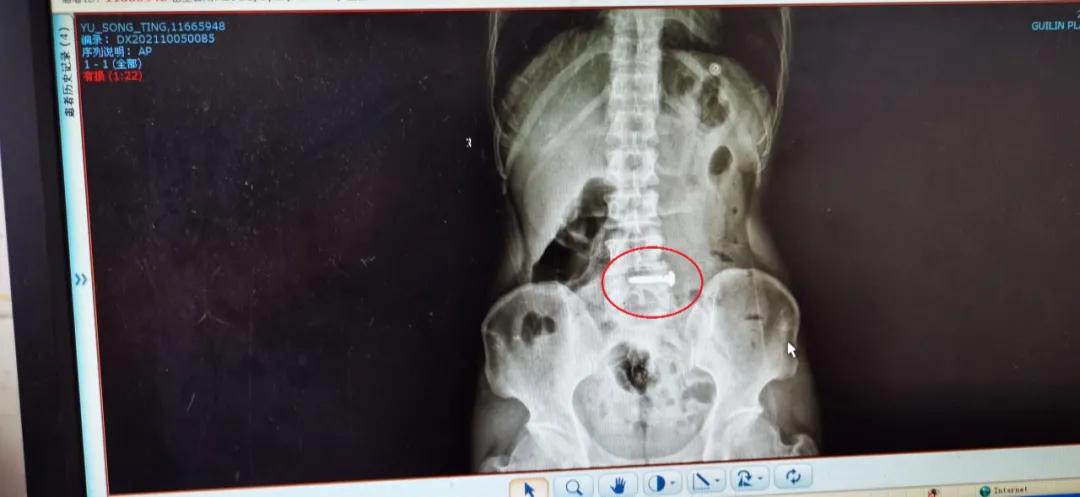

民警对于某进行审讯时,于某表现得满不在乎却又十分配合民警的调查。审讯一结束,于某突然语出惊人:“我吞了钉子,你们关不了我的!”民警随即将于某送至医院拍片检查,结果显示,在于某的消化道内有颗铁钉。

原来,于某二十多天前在某工地附近吸了毒,精神恍惚时,正好有两名男子走过来。当时于某以为是警察过来抓他了,为了逃避打击,情急之下他捡起路边的钉子就吞了下去。